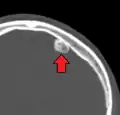

Osteoma of the frontal sinus on CT